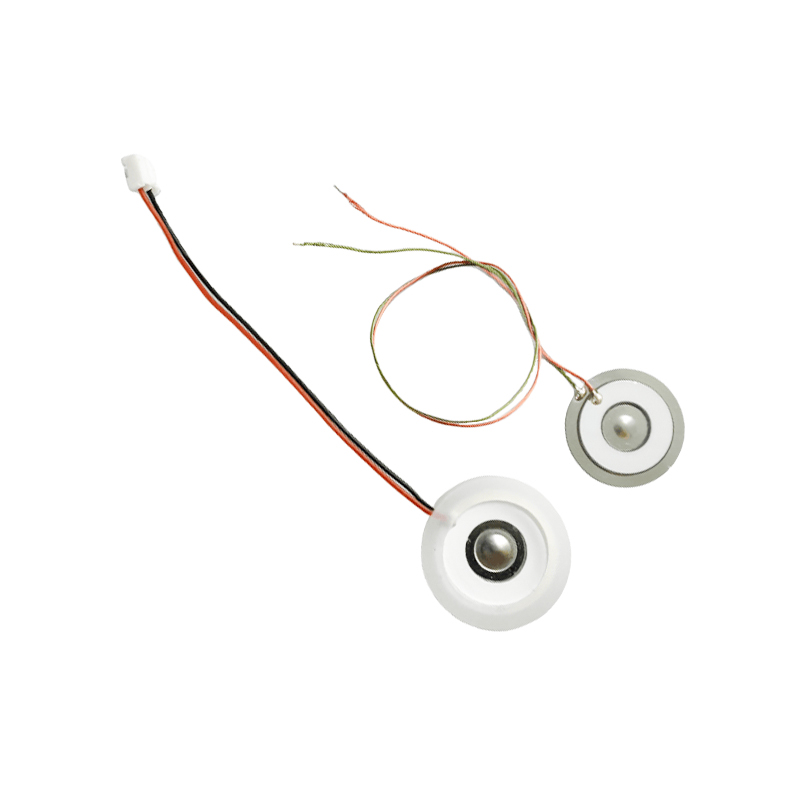

Medyczne tabletki do nebulizatora siatkowego to precyzyjne elementy stosowane w urządzeniach medycznych do przekształcania leków lub roztworów w drobne cząsteczki aerozolu w celu leczenia różnych chorób układu oddechowego, takich jak astma i przewlekła obturacyjna choroba płuc (POChP) itp., poprzez inhalację. Konstrukcja i dobór materiału arkusza nebulizatora mają kluczowe znaczenie dla zapewnienia skutecznego podawania leku i komfortu pacjenta. Arkusz membrany ze stali nierdzewnej jest dziurkowany w blasze stalowej tysiącami drobnych otworów o oczkach 2-3 μm za pomocą technologii wiercenia laserowego w precyzyjnym procesie laserowym, a następnie jest ściśle połączony z okrągłym arkuszem ceramicznym piezoelektrycznym, który przekształca częstotliwość rezonansową arkusza piezoelektrycznego w energię wibracji o wysokiej częstotliwości poprzez sygnał wyjściowy płytki sterownika PCB i szybko rozkłada płynny lek na drobne cząsteczki aerozolu. Krople te nazywane są również medianą wielkości cząstek. Gdy mediana wielkości cząstek D50 osiąga >60% lub więcej, cząstki będą wystarczająco małe, aby podczas oddychania móc dotrzeć głęboko do płuc do powierzchni pęcherzyków płucnych, poprawiając w ten sposób skuteczność wchłaniania leku i efekt terapeutyczny. Arkusz nebulizatora z mikrosiatką medyczną ma głównie kilka form, arkusz nebulizatora z mikrosiatką ze stali nierdzewnej, arkusz nebulizatora medycznego z niklowo-palladem, arkusz nebulizatora medycznego z polimeru PI i tak dalej. Wszystko powyższe odbywa się poprzez piezoelektryczną konwersję energii wibracji ceramicznych w celu osiągnięcia efektu atomizacji.

Poliimid (poliimid) określany jako PI to najlepsze kompleksowe działanie organicznych materiałów polimerowych, ma doskonałą stabilność chemiczną i może wytrzymać korozję różnych leków, aby zapewnić długotrwałe użytkowanie rozpylonych tabletek. Ponadto stabilność termiczna folii polimerowej PI jest również doskonała, przy długotrwałym stosowaniu w zakresie temperatur -200 ~ 300 ° C, wysokiej izolacji, ochronie środowiska i nietoksyczności, jako specjalny materiał inżynieryjny, szeroko stosowany w mikroelektronice lotniczej, membranach do separacji nano-ciekłych kryształów i innych dziedzinach, został włączony w XXI wieku przez kraje do jednego z najbardziej obiecujących materiałów inżynieryjnych i nie jest łatwo go osiągnąć zdeformowany w procesie dezynfekcji wysokotemperaturowej, aby mieć pewność, że produkt zostanie ponownie użyty! Ze względów seksualnych i bezpieczeństwa używamy technologii laserowej do perforacji laserowej, folii PI wszczepianej pomiędzy stal nierdzewną a arkusz piezoelektryczny, stosowania piezoelektrycznej ceramicznej technologii ultradźwiękowej, dzięki czemu rozpylone kropelki przez folię PI rozpraszają się w atomizacji cząstek o wielkości 3 ~ 4 μm do inhalacji nebulizacyjnej medycznej, bezpieczeństwo uwielbiane przez większość użytkowników, wykonane z nebulizatora z Główną zaletą PI jest brak zatykania, wewnętrzna ściana otworu jest gładka i zaokrąglona, brak pozostałości cieczy, atomizacja drobna i stabilna. Atomizacja jest delikatna i stabilna. Tabletki do nebulizacji z folią PI mogą skutecznie zapobiegać pozostałościom leków, zmniejszać ryzyko zanieczyszczenia krzyżowego. W praktyce odzwierciedlono również niskie zużycie energii przez tabletki do nebulizacji z membraną polimerową PI, podsumowując, tabletki do nebulizacji z membraną polimerową PI dzięki swoim doskonałym właściwościom użytkowym i zaletom konstrukcyjnym stały się nieodzowną częścią dziedziny medycznej terapii nebulizacyjnej.

Rozpylacz ultradźwiękowy to urządzenie wykorzystujące zasadę wibracji ultradźwiękowych (konwersji energii) do zamiany cieczy na drobne kropelki. Zasadą działania są unikalne właściwości piezoelektryczne ceramiki piezoelektrycznej. Element atomizujący odbierający odpowiednie wzbudzenie sygnału pola elektrycznego wytworzy odpowiednią częstotliwość oscylacji, poprzez rolę wibracji o wysokiej częstotliwości kawitacji cieczy wyrzucanej z powierzchni wody w celu wytworzenia rodzaju cząstek mgły wodnej, atomizowanych dużą liczbą jonów ujemnych i małych cząstek cząsteczek, może osiągnąć wzrost wilgotności otoczenia, rolę świeżego powietrza. Powierzchnia atomizera jest pokryta emalią szklistą o wysokiej temperaturze 800 stopni, aby chronić srebrne elektrody arkusza piezoelektrycznego, zwiększyć odporność atomizera na kwasy i zasady oraz odporność na utlenianie, a także zwiększyć żywotność atomizera. Szeroko stosowany w nawilżaczach wewnętrznych, oczyszczaczach powietrza, leczeniu nebulizatorami medycznymi i samochodach kosmetycznych, e i innych dziedzinach, ale nadaje się również do magazynów, fabryk, nawilżania, dezynfekcji, aby stworzyć atmosferę sprzętu nawilżającego. Tabletki zamgławiające stosuje się głównie w nawilżaniu przemysłowym, zamgławianiu medycznym, zamgławianiu aromaterapeutycznym, nawilżaniu środowiska, zamgławianiu ogrodu i innych scenach.